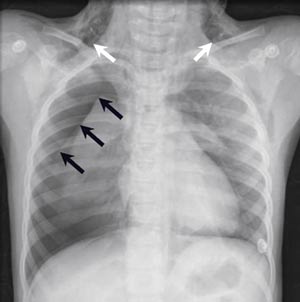

Kontroll røntgen viste ekspansjon av høyre lunge som stod i vegg, men det var nå tilkommet pneumothorax på venstre side (fig 2). Det ble lagt inn thoraxdren også på venstre side, og nytt bilde viste nå at begge lungene stod i vegg. Pasienten fikk bredspektret antibiotikaprofylakse, særlig for å forhindre mediastinitt.